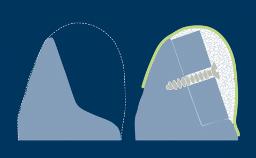

Quando um dente é extraído, o osso alveolar que suporta o dente é reabsorvido ao longo do tempo. Essa reabsorção resulta em uma redução no volume ósseo alveolar, como mostrado neste exemplo clínico de um incisivo central superior direito ausente. O osso diminuiu significativamente na largura orofacial, e isso está em conflito com o requisito fundamental da implantodontia de que os implantes são instalados na posição correta determinada pela prótese dentária. Quando o osso alveolar é reabsorvido, muitas vezes é necessário aumentá-lo para garantir que os implantes possam ser instalados corretamente e completamente incorporados ao osso. Este módulo descreverá uma técnica específica para aumento ósseo conhecida como regeneração óssea guiada ou ROG.